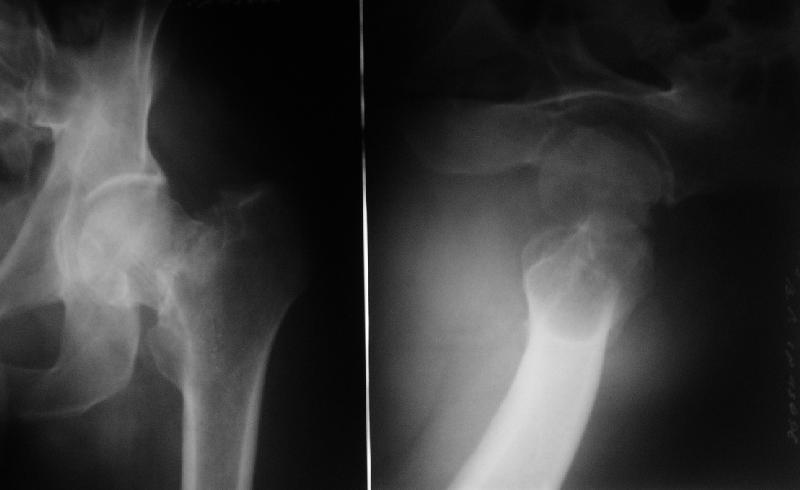

Нелеченный перелом шейки бедра

Поступил пациент 50 лет, из области. Травма 18.08.08. Лечили консервативно.

Сейчас вот чего-то спохватились и направили. Движения в тазобедренном суставе практически безболезненны, кроме форсированной внутренней ротации. В остальном проблем со здоровьем нет.Рентгенограмма в приложении. Видимо, выбирать приходится в первую очередь между вальгизирующей остеотомией и эндопротезированием.

Dear All,A male 50 years old referred to our institution from a rural hospital. Injured Aug 18. Managed nonoperatively. Hip motions are pain free except forced internal rotation. No other comorbidities.Images attached. Looks like main options are valgus osteotomy or THA. What would be optimal? Any other ideas? THX!

My impression from that x-ray is that the head is avascular. I'd get a bone scan to assess viability.

На R-гр. в прямой проекции очень явственно виден малый вертел, что свидетельствует об избыточной наружной ротации бедренной кости. А по тексту следует фиксированная ротация. Возможно, следует провести дополнительное R-обследование.

По снимкам могу предположить, что укорочение составляет ~ 2,0 - 2,5 см и варусная деформация около 7 - 10 градусов. Вероятно, в дальнейшем такое смещение больного может и не беспокоить.